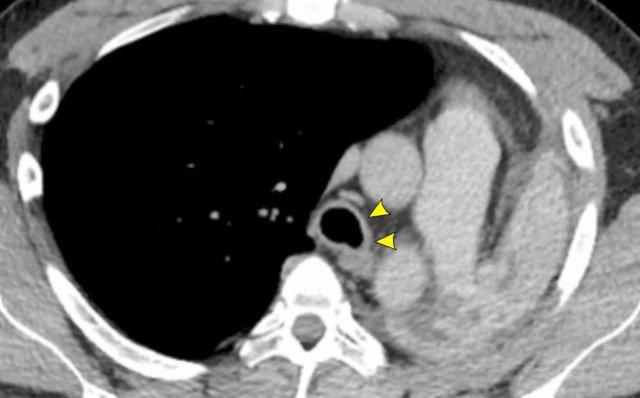

Tổn thương đường thở trung tâm trong GPA cho thấy dày thành khí quản theo chu vi ở mức carina ở bệnh nhân nam 43 tuổi. Có xẹp phổi trái do tổn thương mạn tính của phế quản gốc trái gây hẹp lòng.

Bệnh amyloid

Hình ảnh

Bệnh amyloid khí quản-phế quản ở bệnh nhân nữ 61 tuổi, cho thấy dày thành đường thở không đều với các ổ đậm độ cao và vôi hóa gây hẹp lòng đáng kể phế quản gốc phải.

Nội soi phế quản cho thấy các tổn thương không đều màu vàng điển hình.